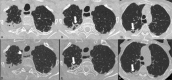

Pleuroparenchymal fibroelastosis in patients affected by systemic sclerosis: What should the rheumatologist do?

Pleuroparenchymal fibroelastosis (PPFE) is a rare new interstitial lung disease (ILD) characterized by the fibrotic thickening of the visceral pleura and subadjacent parenchymal areas of the upper lobes This study reveals that patients with ILD-SSc associated with chest HRCT evidence of PPFE require close and recurrent follow-up with periodic evaluation of lung function parameters, DLCO and chest HRCT. Rheumatologists should be aware of this new radiological finding which is accompanied by a negative prognosis, especially when associated with a progressive course. Patients with this radiological pattern need to be monitored with particular attention.